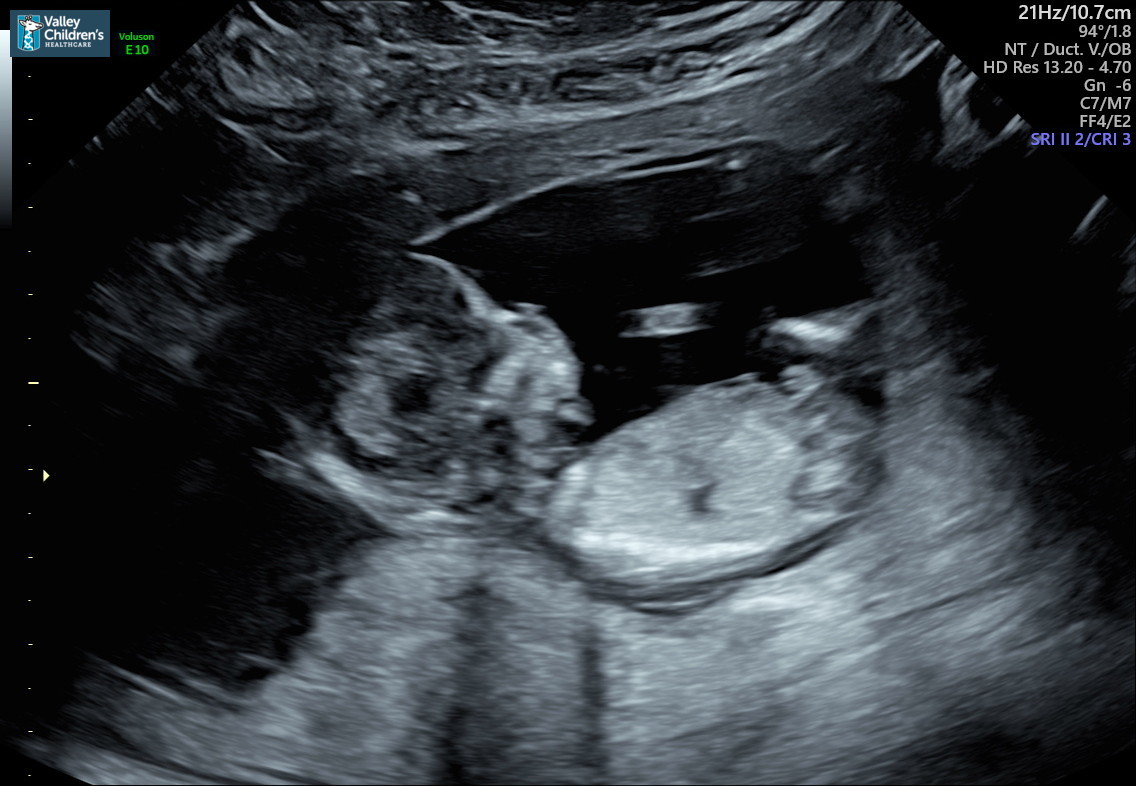

Hello all me and my wife are pregnant with our second and we’re on the fence and can’t tell if a boy or girl?? Any help would be appreciated these pictures will be from 12W 4D, thanks in advance:)Attachment 41451Attachment 41452

Looks boyish to me 😊

That's too early for me to feel confident guessing. Gorgeous baby though!